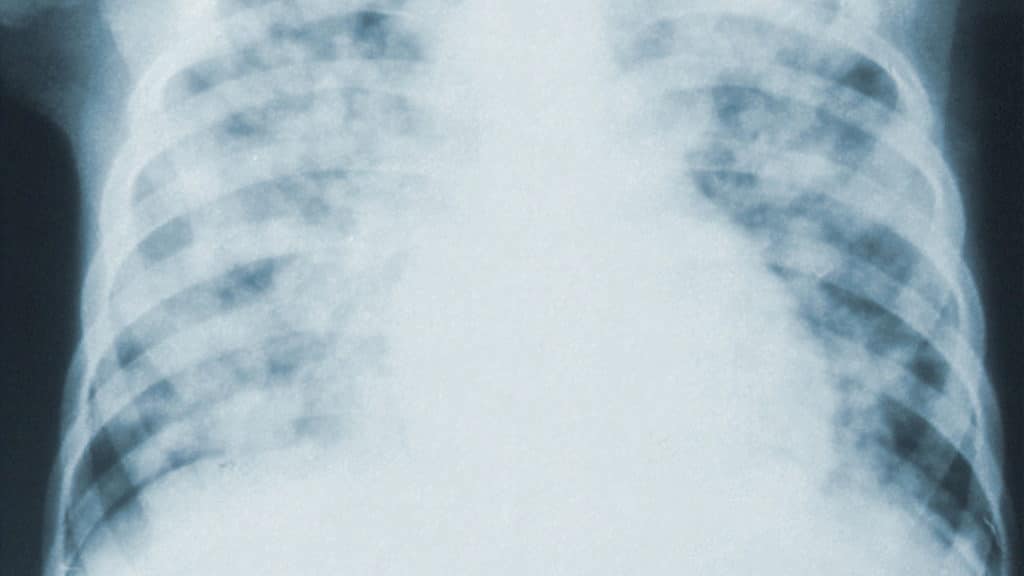

Air pollution caused conditions: the risk of co-morbidities

These conditions affect millions of people, and can increase the risk of more serious health complications if one contracts COVID-19.